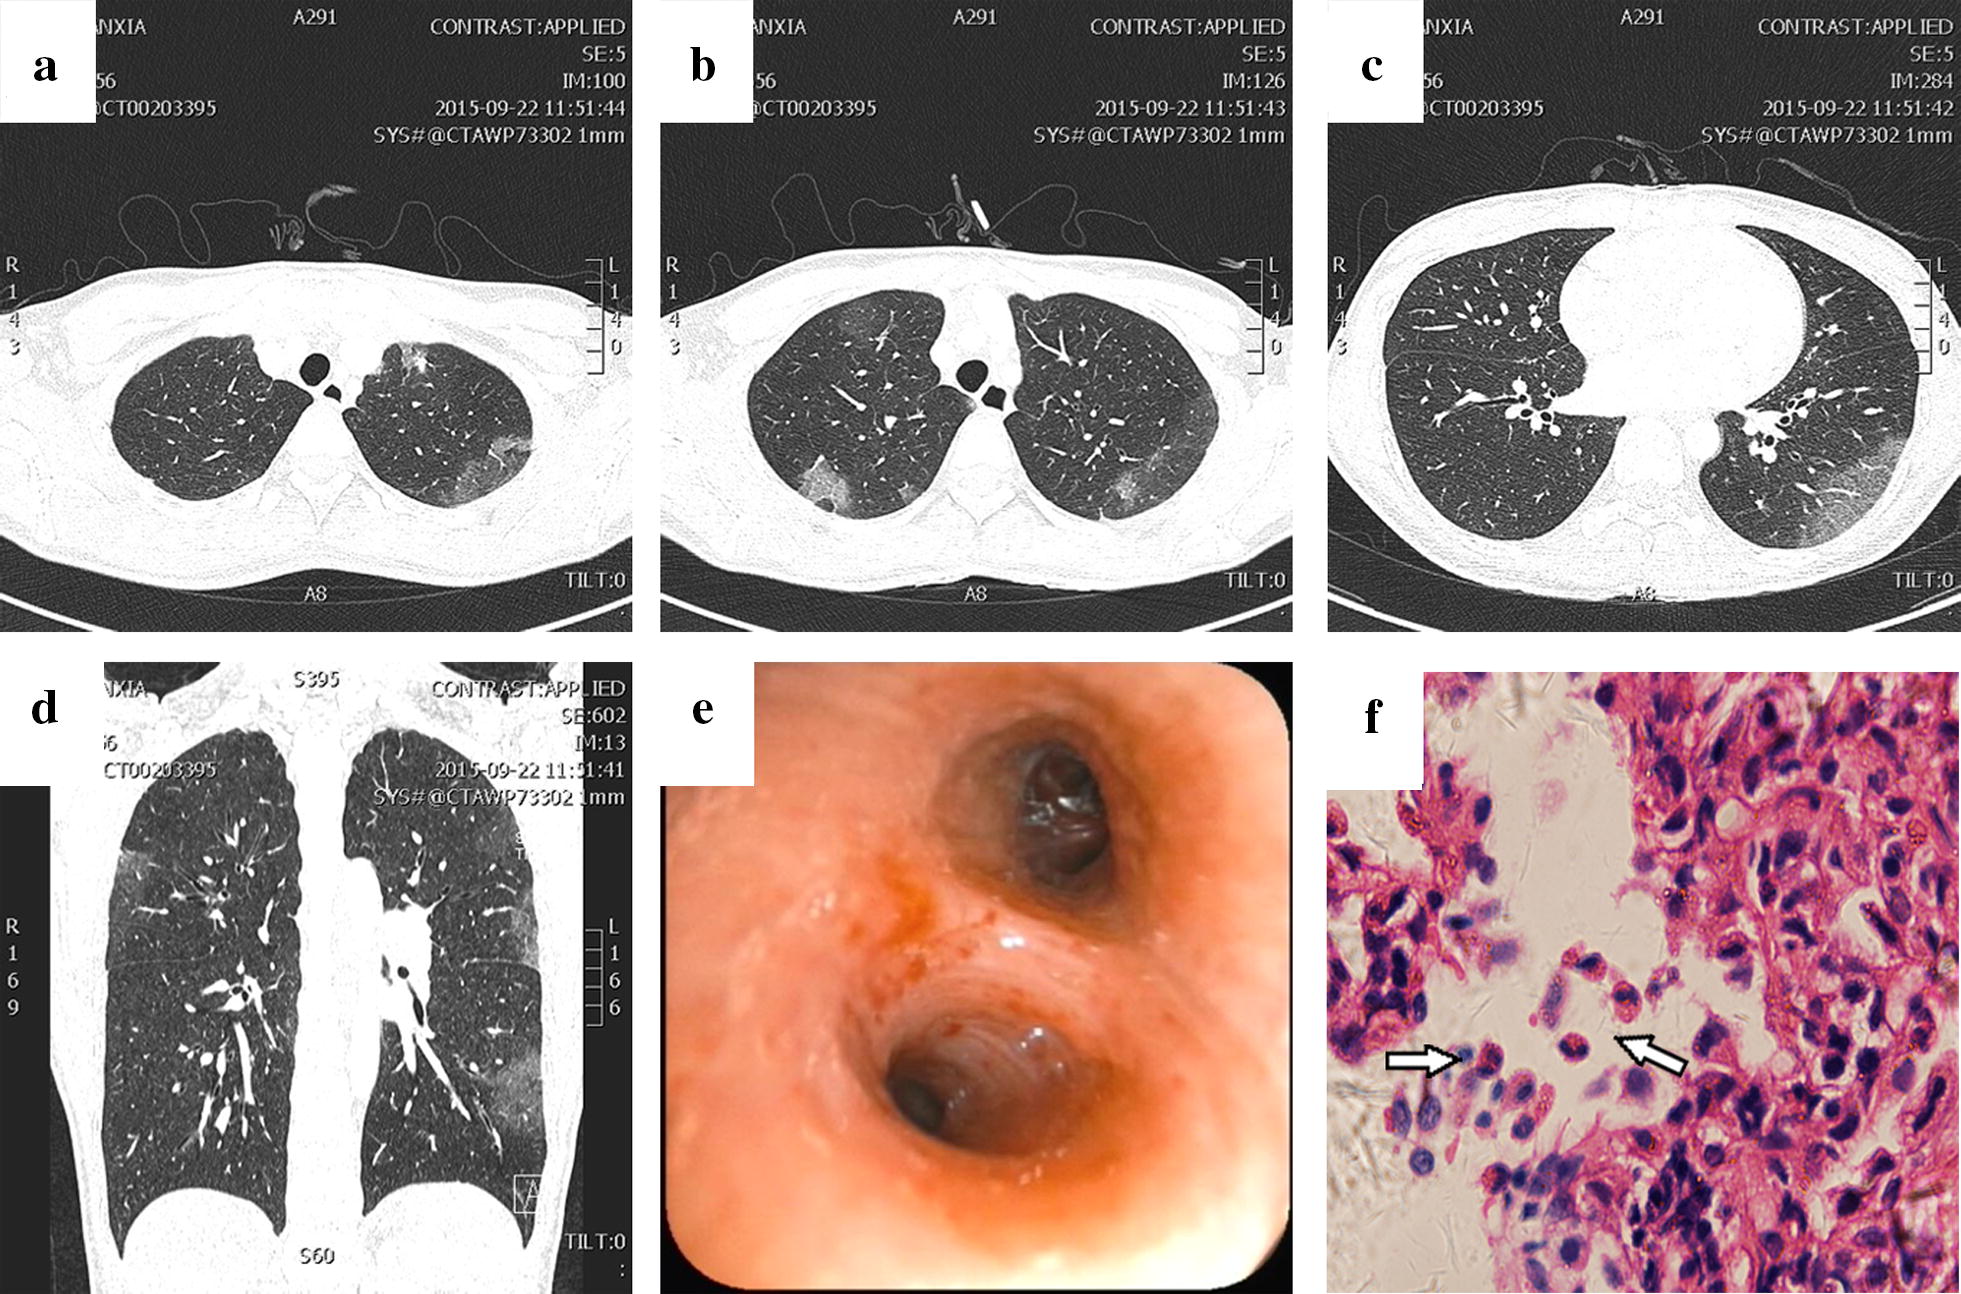

Shortterm pulmonary infiltrate with eosinophilia caused by asthma a Severe Asthma With Eosinophilic Phenotype — this article reviews the current evidence and challenges for defining, diagnosing and treating severe. — eosinophilic asthma is now recognized as an important subphenotype of asthma based on the pattern of. — patients with severe asthma present with a variety of clinical histories, physiologic changes (beyond changes in. — adult patients with severe asthma and. Severe Asthma With Eosinophilic Phenotype.

From www.researchgate.net

(PDF) Shortterm pulmonary infiltrate with eosinophilia caused by Severe Asthma With Eosinophilic Phenotype — patients with severe asthma present with a variety of clinical histories, physiologic changes (beyond changes in. — adult patients with severe asthma and available blood eosinophil count (bec) from 11 countries enrolled in the international severe. — this article reviews the current evidence and challenges for defining, diagnosing and treating severe. — eosinophilic asthma is. Severe Asthma With Eosinophilic Phenotype.

From www.semanticscholar.org